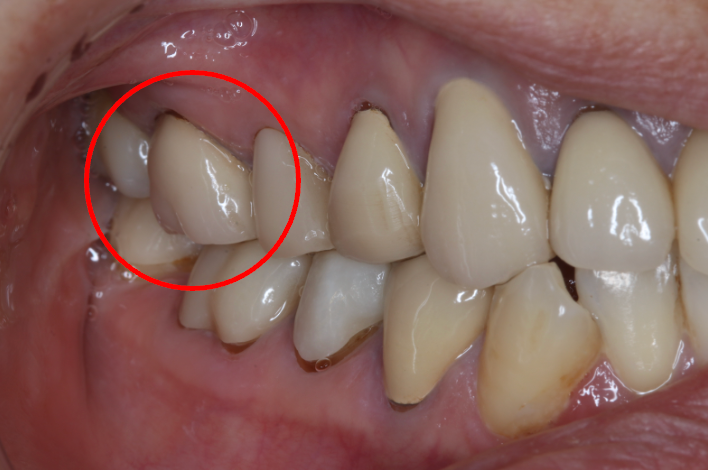

セラミック症例①

年齢40代女性

治療期間1ヶ月

治療内容ジルコニア、セラミックインレー、セラミッククラウン

治療箇所左上1番、2番 左下5番、7番 右上1番、2番、3番、4番、5番 右下5番、6番、7番

治療費用100,000円